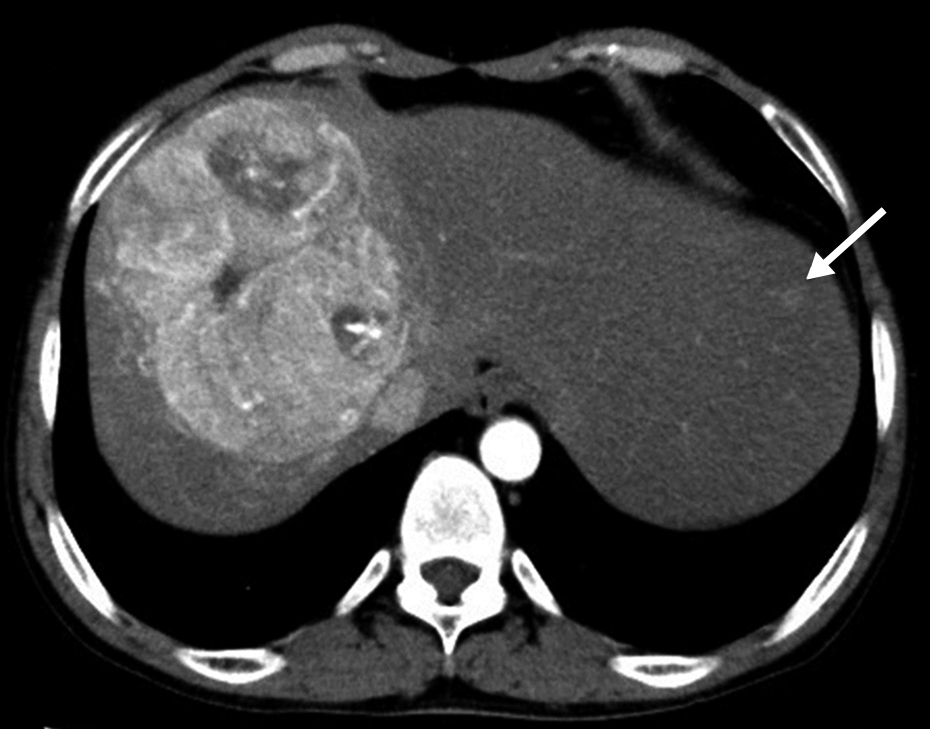

初診時CT所見:著明な肝腫大を認めた.肝右葉に,動脈相で早期濃染され,平衡相でwash outされる,径11 cmの腫瘍を認めた.肝S2にも動脈相で早期濃染される小病変を認めた(Fig. 1a).

Enhanced CT findings at the first visit. a) Arterial phase. The tumor is enhanced in the right robe. The small tumor is enhanced in segment 2 (arrow). b) Equilibrium phase. The tumor displaces the right hepatic vein (arrowhead) and the middle hepatic vein (arrow).

以上より,肝細胞癌と診断した.主腫瘍は右肝静脈と中肝静脈を圧排しており,下大静脈にも広範に接していたため(Fig. 1b),肝動脈化学塞栓術(transcatheter arterial chemoembolization;以下,TACEと略記)を2回施行した.初回はシスプラチンを使用し,3か月後にシスプラチン,リピオドール®を使用して2回目のTACEを施行した.TACE後,腫瘍は径7 cmに縮小し,主要血管の圧排所見が改善したため,右門脈塞栓術(percutaneous transhepatic portal embolization;PTPE)の後に肝右葉切除を施行する方針とした.